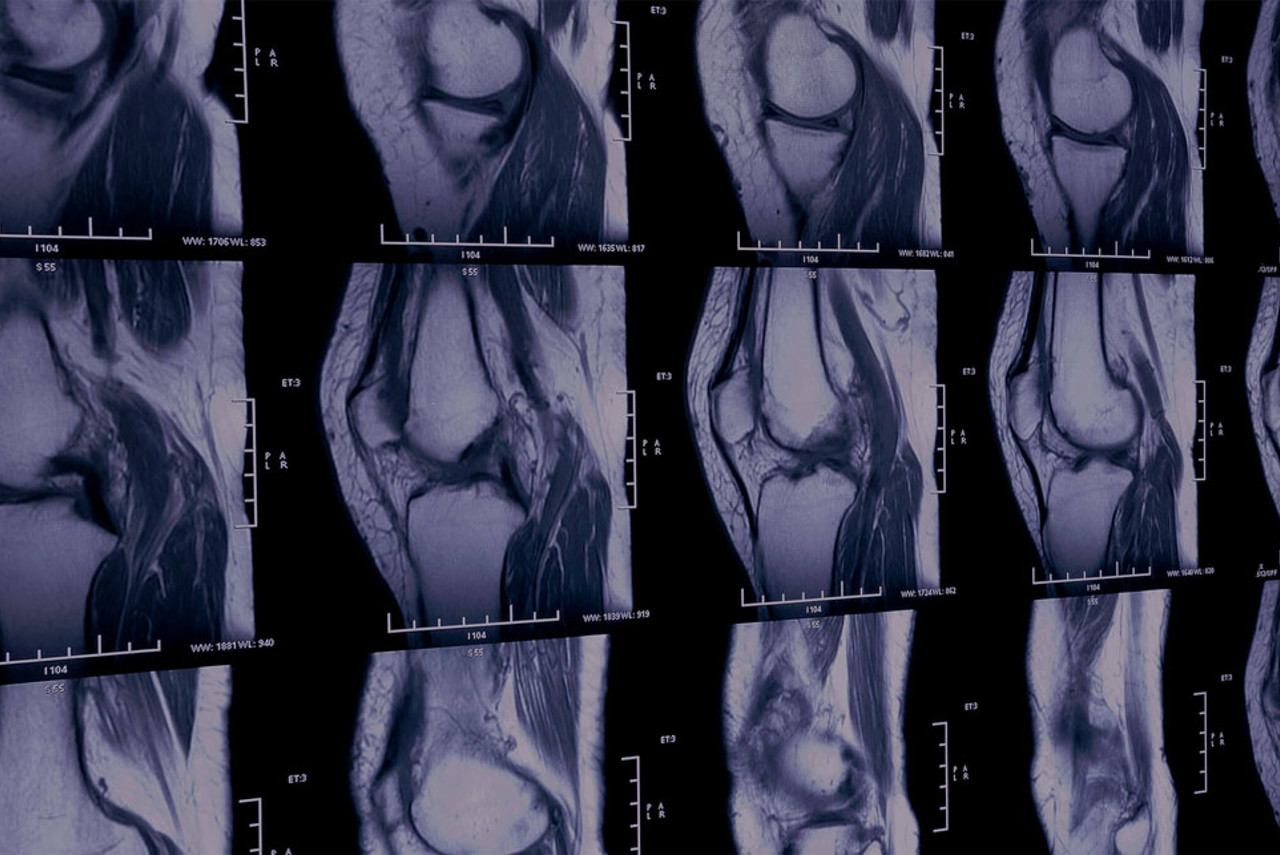

This scan can help diagnose various conditions, including tendonitis, bursitis, carpal tunnel syndrome, rotator cuff injuries, ligament tears, and joint problems. It’s also useful for identifying sports injuries or growths like cysts and tumours.